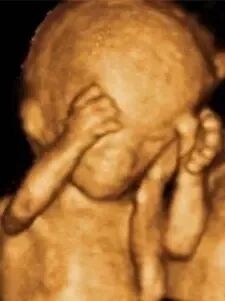

(四维彩超图)